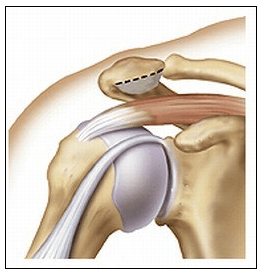

Il s’agit d’une inflammation des tendons de l’épaule, accompagnée d’une calcification visible sur les radiographies.

Il consiste à retirer sous arthroscopie (caméra) la calcification et de réaliser parfois en complément une acromioplastie (« fraiser » l’os juste au dessus du tendon pour permettre au tendon de glisser sans accroc)